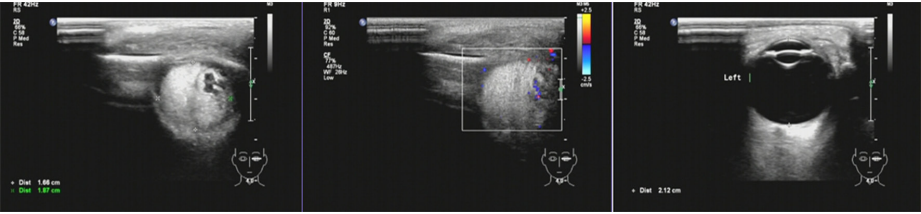

图 3 治疗后眼部彩色 B 超图像

Figure 3 Color B-ultrasound image of the eye after treatment

患儿,男, 3岁,因“左眼红肿12 d ”就诊。患儿就诊前1个月有感冒病史。2019年4月1 8日,患者出现左眼眼睑红肿,当地医院诊断“左眼睑炎”,予以头孢咪唑2 g每天1次、地塞米松磷酸钠5 mg每天2次静脉滴注2 d后,症状好转后反复。2019年4月29日再次于外院眼科门诊就诊,眼眶及视神经MRI显示:1)左眼上睑软组织肿胀,考虑炎性改变;2 )左眼上直肌轻度增粗;左侧泪腺较对侧增大(图1A)。建议活检明确诊断。患者家属拒绝活检。同日就诊暨南大学附属第一医院眼科门诊,眼部检查示:左眼眼睑红肿(++++),眼眶鼻侧可触及约黄豆大小硬结,界不清,质地中等,压痛(?),伴上睑下垂,遮盖角膜下缘(图2)。双眼眼位正,左眼眼球外转轻度受限。辅助检查:降钙素原>0.1 ng/mL,循环免疫复合物>110,CRP+风湿4项+免疫球蛋白+补体7项未见异常。结合患者眼部症状及影像学资料,诊断为“左眼特发性眼眶炎性假瘤”。血液内科会诊排除血液系统恶性疾病后,予以全身静滴地塞米松磷酸钠2.5 mg[0.25 mg/(kg·qd)],局部抗炎、护胃等对症治疗。48 h后患者左眼下睑可自行抬高距离角膜下缘约2 mm。治疗6 d后复查,降钙素原<0.1 ng/mL,血常规:WBC<10×1 09/ L,生化八项未见异常。眼部B超(2019年5月5日;图3 ):左眼内上方见1.7 cm×1.9 cm占位病变,边界清,形态欠规则,内回声欠均匀,周边可见少许血流信号;右眼未见明显异常。眼眶及视神经MRI(2019年5月9日;图1B):左眼上直肌、左上眼睑及邻近软组织肿胀较入院时明显好转,呈长T 1、长T 2信号。住院治疗9 d后,患者左眼眼睑炎性症状好转,呈中度上睑下垂,眼眶鼻侧硬结较入院减小,双眼眼位正,左眼眼球运动正常,出院后继续口服泼尼松15 mg[1.5 mg/(kg·qd)],维持1周后每周逐渐减1.25 mg直至停药。患儿出院1周后复诊,查体左眼眼眶鼻侧未触及明显硬结,上睑下垂症状消失,双侧睑裂对称。